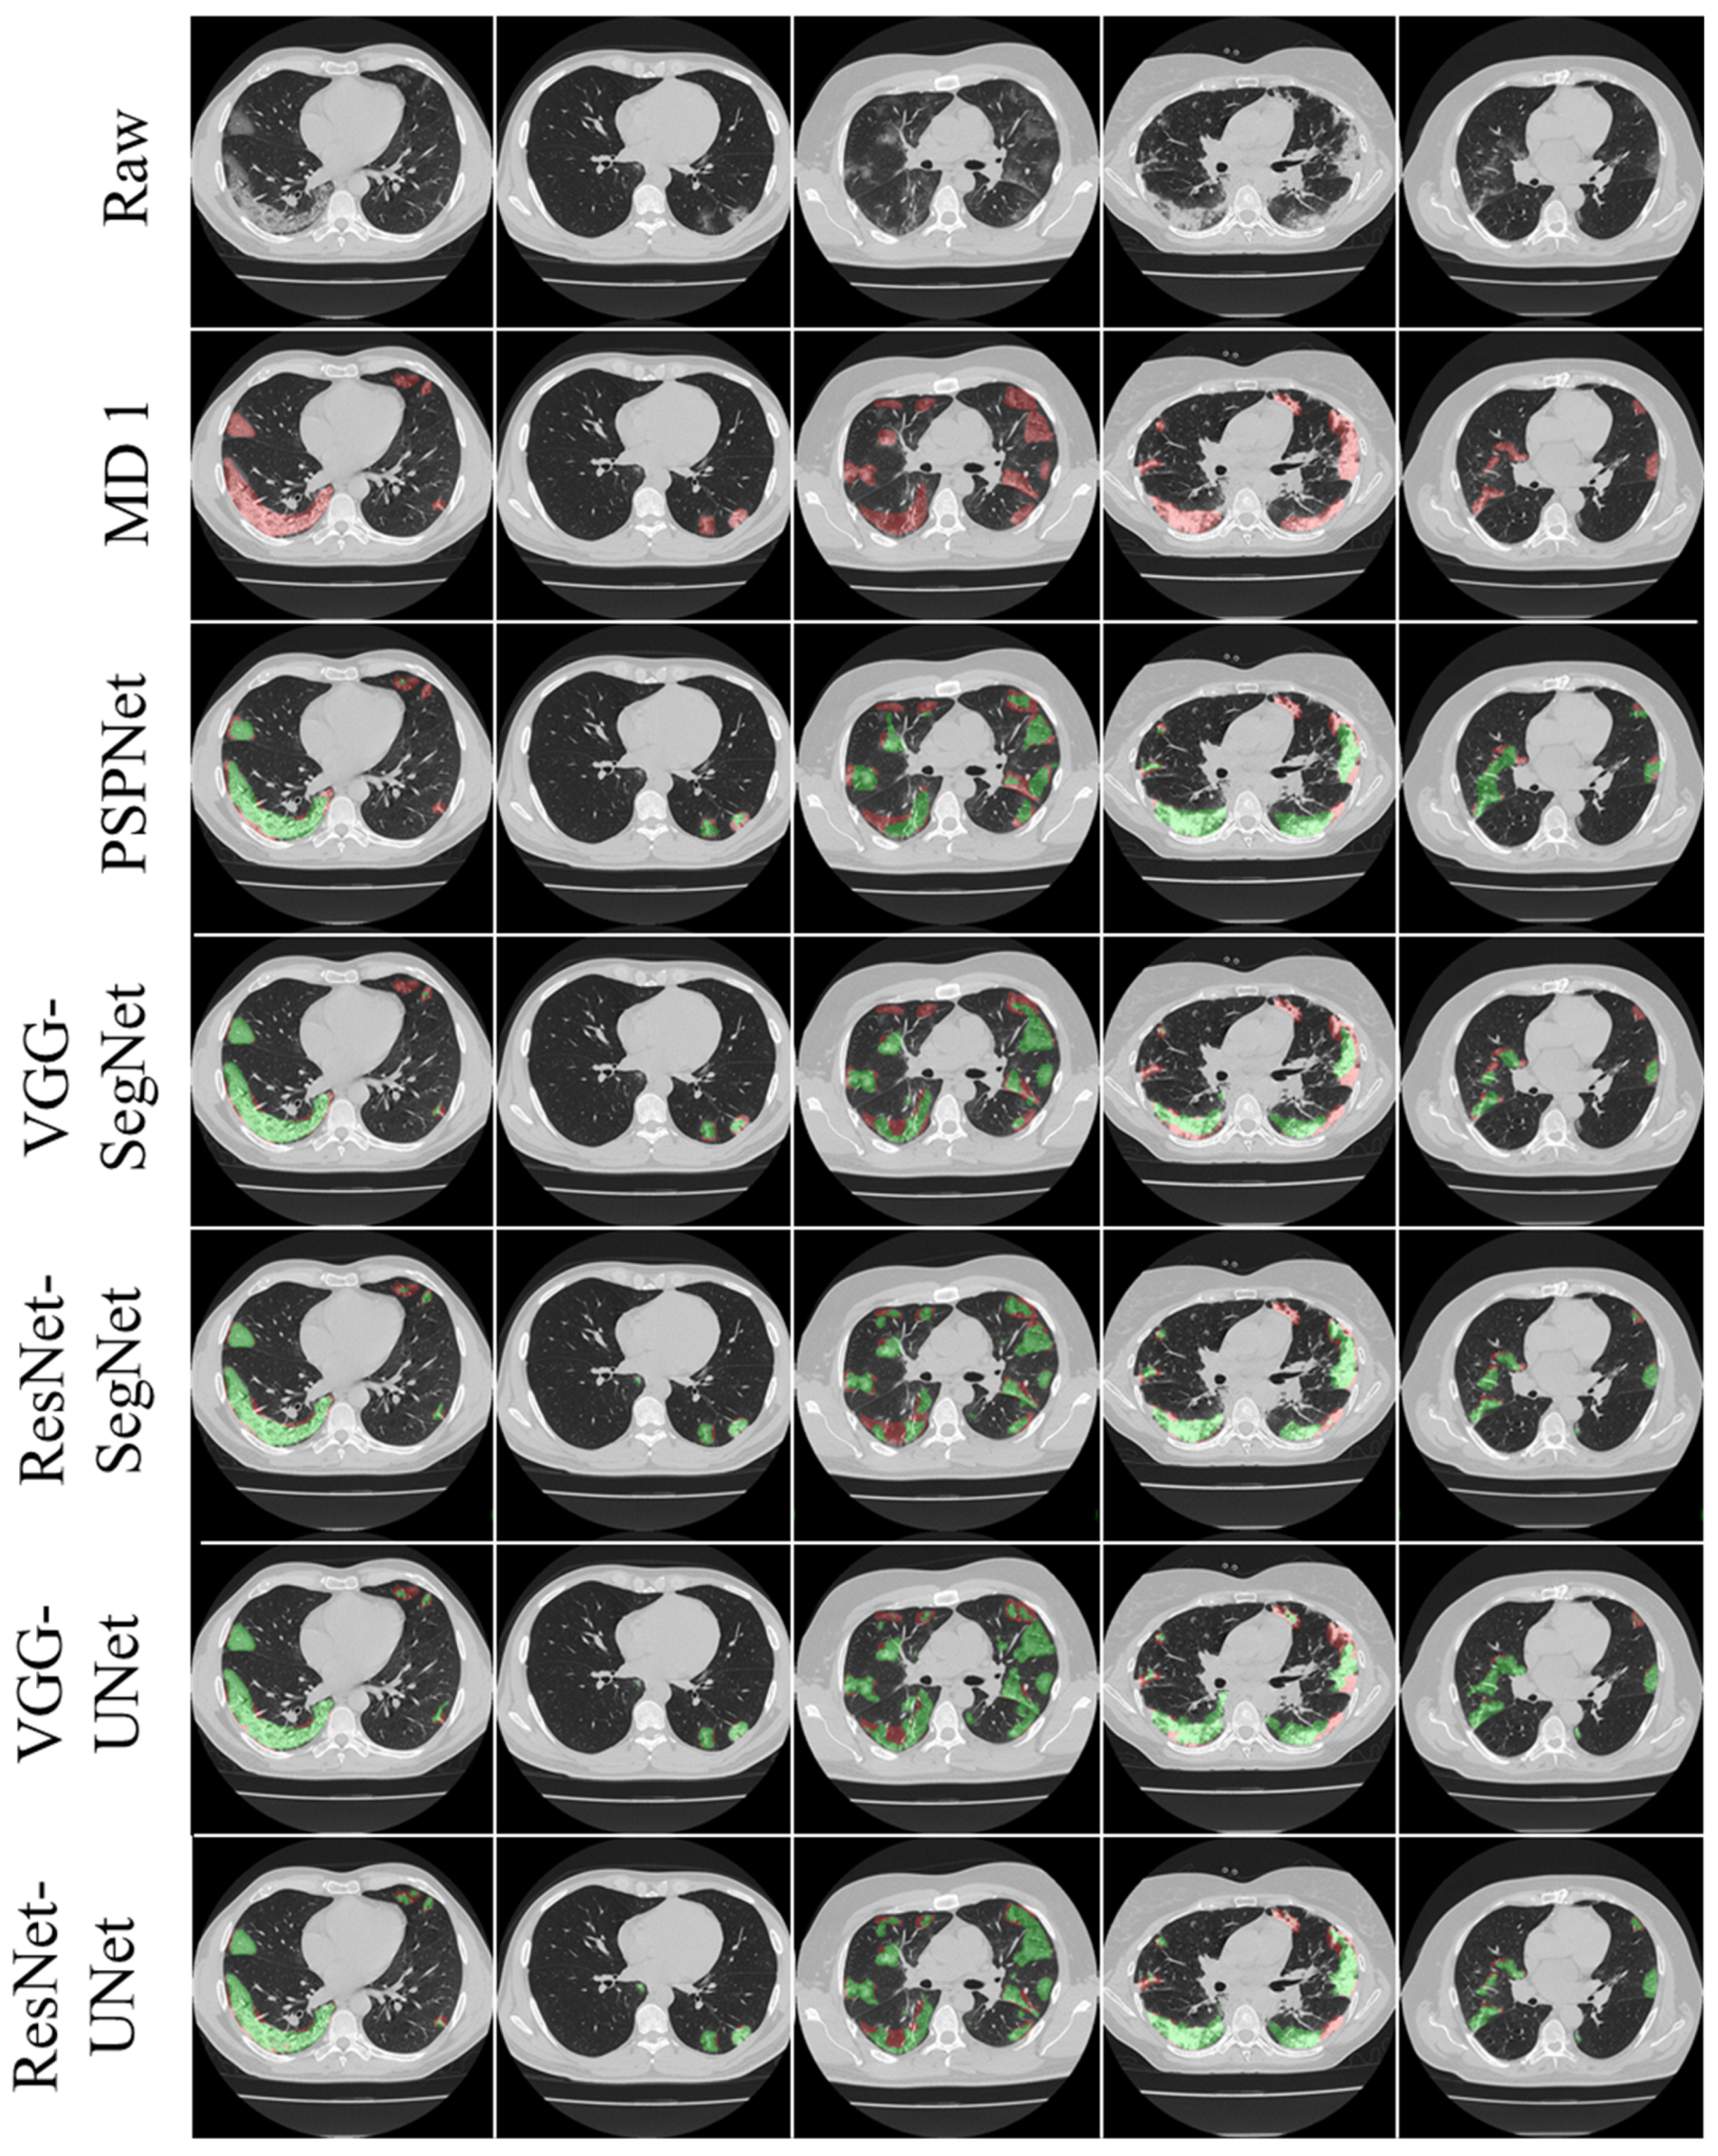

3.1. Results

3.2. Performance Evaluation